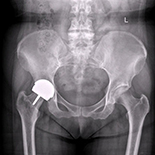

Metal-on-metal resurfacing arthroplasty is an attractive alternative to conventional total hip arthroplasty in patients with osteoarthritis secondary to developmental dysplasia of the hip (DDH). The purpose of this study was to assess the mid-term clinical outcome and mid-term survivorship of Metal-on-metal resurfacing arthroplasty in patients suffering from osteoarthritis secondary to DDH.

Between May 2003 and Dec. 2005, 15 operations using ASR™ and 19 using Corin were performed in 29 patients to treat advanced osteoarthritis secondary to DDHs. There were 6 males (20.7%) and 23 females (79.3%), with an average age of 47.2 years (range, 36–64 years). Clinical and radiographic results were observed. All patients were followed up at the 1st, 2nd, 3rd, 6th, and 12th months after surgery and annually thereafter.

The overall survival was 88.2% at a minimum follow-up of 8 years, but the survival was 91.2% after excluding the infections as the cause of component loosening and failure. The mean Harris hip score improved from 48.27±3.13 (range, 14–71) to 89.63±3.42 (range, 65–100) at latest follow-up. The flexion was from 75.14±8.05° to 107.21±9.34. Only 4 failed because of deep infection, femoral neck fracture, and aseptic loosening.

Metal-on-metal resurfacing arthroplasty showed perfect results at a minimum of 8-years of follow-up in our study, and may be a reasonable option for osteoarthritis secondary to developmental dysplasia of the hip (DDH).